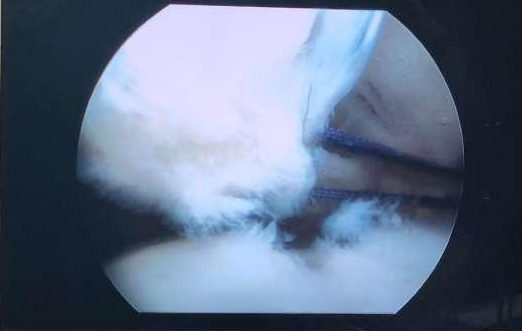

五、肩关节镜肩袖肌腱损伤手术技术。肩关节大师Avi Chezar教授对肩关节的深入理解、对关节镜的熟练操作,着实让我大开眼界。从Avi Chezar教授身上,我学到的不仅仅是更精湛的手术技术,更多的是先进的手术理念、对手术的思考方式、如何去对手术做全面的评估与设计。

七、全关节镜下Latarjet手术。复发性肩关节脱位、肩关节不稳的治疗是世界性难题,如何稳定患者的肩关节、避免肩关节脱位的复发非常具有挑战性,其治疗目前尚未有高度凝聚性的共识。在EMEK医学中心,Avi Chezar教授成熟开展的全关节镜下Latarjet手术,极大地降低了患者肩关节脱位的复发率,让肩关节不稳这一世界难题变得不再那么遥不可及。